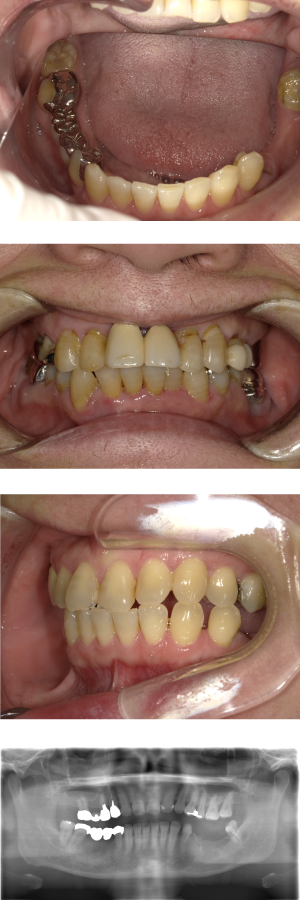

50代 インプラント治療(右上3左上3のみGBR)

| 年代・性別 | 50代・男性 |

| 主訴 | 入れ歯が合わず毎日ヨーグルトしか食べることができないので、しっかり咬めるインプラントにしたい。 |

| 部位 | 右下⑦⑥5④ 上顎③2①①2③ 左下67 |

| 治療期間 | 約9ヶ月 |

| 費用 | ¥4,273,500(税込) |

| 副作用・リスク |